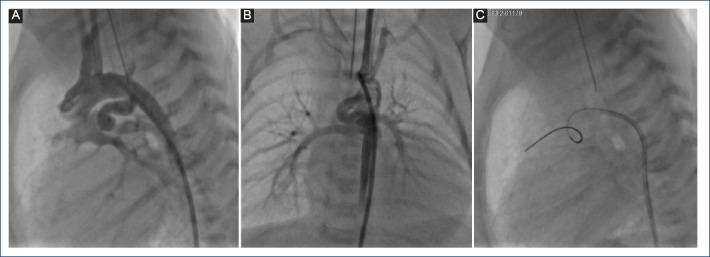

Objectives: Patients with congenital heart disease with ductus arteriosus-dependent pulmonary flow have as a palliative procedure the placement of a Blalock-Taussig-Thomas fistula (BTTF) or ductal stent (DSt) and subsequently undergoing to definitive palliation or repair. BTTF has been associated with increased morbidity and mortality. The objective of this research is to compare the morbidity and mortality of BTTF versus DSt, as well as their short- and medium-term outcomes.

Methods: The study population was patients undergoing BTTF or DSt placement from January 2012 to December 2022.

Results: 164 patients were identified, 128 with BTTF and 36 with DSt. 87.5% of the BTTF group presented complications, and 22.2% of the DSt group (p < 0.001). The OR for BTTF for development of complications was 19.58 (95%CI: 7.79-51.17). Intensive care unit stay was shortzer in DSt compared to FBTT (MD: -4.69 days; 95%CI: -7.30 to -2.07; I2 = 80%; p = 0.0004). The relative risk of FBTT patients for death was 2.32 (95%CI: 0.755-7.149), but there was no statistically significant difference for mortality (p = 0.135).

Conclusions: Mortality presented a lower tendency in patients with DSt. However, in other variables such as morbidity, hospital stay and reintervention were less frequent in the DSt group and were statistically significant. This evidence is the first in Latin-America and supports DSt as the safest and most effective option compared to FBTT in our setting.